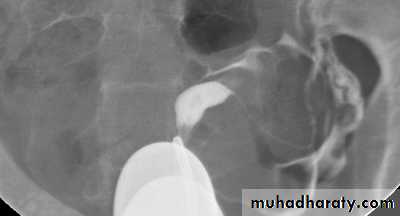

male &female reproductive tractsmammogram

genital tract and mammogram